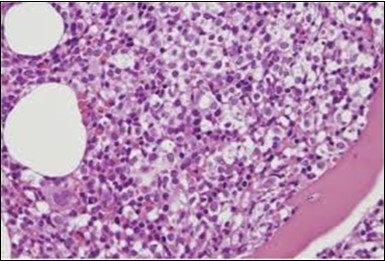

The classic hairy cell is medium sized with a magnitude of 10-14µm. The moderately abundant or variable cytoplasm may be transparent or mildly basophilic. The cellular surface with the characteristic serrated perimeter depicts innumerable fragile or stout extensions of cytoplasm ,particularly discernible on the phase contrast and electron microscopy. The cytoplasm may exhibit vacuoles with occasional azurophilic granules4. The nucleus may be elliptical or reniform, folded or indented with a coarse, reticulated or a finely dispersed chromatin and inconspicuous nucleoli along with infrequent mitosis. Bone marrow aspiration or bone marrow trephine biopsy may be inadequate for diagnosis in 30%-50% individuals4. The trephine sections of the bone marrow may depict a characteristic interstitial pattern of leukaemic infiltration. Generally the bone marrow is hyper-cellular, though it may be hypo-cellular in 10-15% individuals4. The leukaemia cell ingress may be diffuse or partial, although diffuse infiltration is frequent. The partial variety of leukaemic dissemination may be ineptly categorized with an indeterminate differentiation from the uninvolved marrow. The malignant insertions may initially emerge as miniature, undefined, cellular loci. The formalin fixed, paraffin embedded sections may elucidate a crystalline zone or a “halo” appearance of the cells with a circumscribed nucleus on account of the plentiful cytoplasm4. The cellular margins may be intertwined. Fixation of bone marrow smears with Zenker’s fixative may demonstrate a retracted cytoplasm of the hairy cells with a consequent disconnected structure. The bone marrow in the absence of a malignant process may be hypo-cellular or hyper-cellular. Reticulin stains may delineate an enhanced accrual of broad, dense reticulum fibres surrounding the aggregates of leukaemia cells with the fibrous circumlocution of individual malignant cell and fibrotic extensions into the abutting, uninvolved bone marrow4.

The leukaemia cells may enunciate a characteristic immune phenotype, crucial for a confirmatory diagnosis. The peripheral blood mononuclear B cell population may display a kappa or lambda light chain restriction. The phenotype of classic hairy cell leukaemia may be delineated by concurrent, immune reactive CD19+ CD20+,CD 11c+, CD25+, CD103+ and CD123+. An intensely immune reactive CD200+ and a non reactive CD27- antigen may be present2, 4. Evaluation of a trephine bone marrow biopsy and bone marrow aspirate may define the degree of tumour infiltration. A dry tap on account of prominent bone marrow fibrosis may be elucidated at preliminary diagnosis. A decline in the normal haematopoiesis may account for a hypo-cellular marrow in 10% instances. Gradation of cellular infiltrating of the leukaemia within the bone marrow may be appropriately investigated with immune –histochemical stains2, 4. Immune staining for CD20+, annexin 1 and VE1 (a BRAF V600E stain] may validate the diagnosis and precisely analyse the extent of malignant bone marrow infiltration[8]. Determination of BRAF V600E mutation may be critical in therapeutically non responsive individuals with applicable standard therapy or in instances of multitudinous reoccurrences[9]. Deploying inhibitors of BRAF V600E gene may be efficacious in patients impervious to approved therapy. The mutation necessitates a comprehensive scrutiny of the implicated individuals with a sensitive molecular assay which may discern up to < 10% of the hairy leukaemia cells appearing in the peripheral blood smears or bone marrow aspirates diluted with peripheral blood or aspirates elucidating a dry tap[2,4]. Allele specific polymerase chain reaction (PCR) or a next generation sequencing may be optimally employed to circumvent false negative outcomes. If the leukaemia cells are sparse or if particularly sensitive & efficacious molecular techniques are not accessible, the application of appropriate immune histochemical stains to the bone marrow biopsy such as a BRAF V600E mutation stain (VE1) may detect the hairy cells and conclusively diagnose the condition[2,4,10]. Figure 1, Figure 2, Figure 3, Figure 4, Figure 5, Figure 6, Figure 7, Figure 8, Figure 9, Figure 10, Figure 11, Figure 12, Figure 13, Figure 14.

Figure 9.HCL: hairy cells within a bone marrow trephine biopsy(25).

Figure 10.HCL: inconspicuous nucleoli, open-ended chromatic and surface protrusions(26).

Figure 11.HCL Oral mucosa with soft tissue infiltration of hairy cells(27).